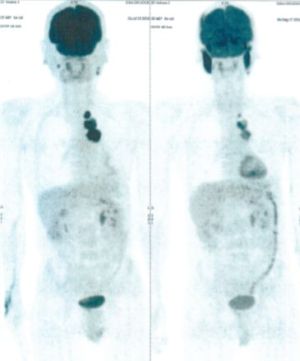

CASE NO: 2 (HEPATOCELLULAR CARCINOMA)

A 40+ man with hepatocellular carcinoma, an incurable cancer. After 2 treatment, the activity of the hepatocellular carcinoma is less.

CASE NO: 2 (HEPATOCELLULAR CARCINOMA) - After a few more treatments

After another few treatment, the activity of the hepatocellular carcinoma is much less. The patient never came back for further treatment, but this case, and case no: 1, shows that incurable hepatocellular carcinoma, often seen in hepatitis B and C patients, can be cured.

CASE NO: 3 (PROSTATE CANCER)

A middle-aged man with castration resistant prostate cancer, having failed all currently available cancer treatment, was very weak, and getting worse every day. The PET/CT scan showed he had massive bone metastases. After a few treatment, all the bone metastases went into remission. About 6 months later, he is still in remission.